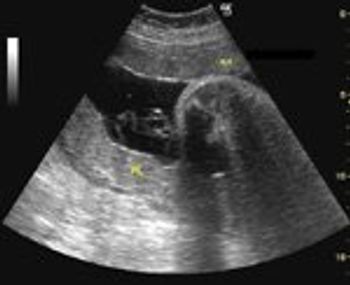

Several recent studies have shown that the addition of secondary ultrasound markers to the combined first-trimester screening for aneuploidies, or chromosomal abnormalities such as trisomy 21 (Down syndrome) and trisomy 18 (Edwards syndrome), can slightly improve screening accuracy.